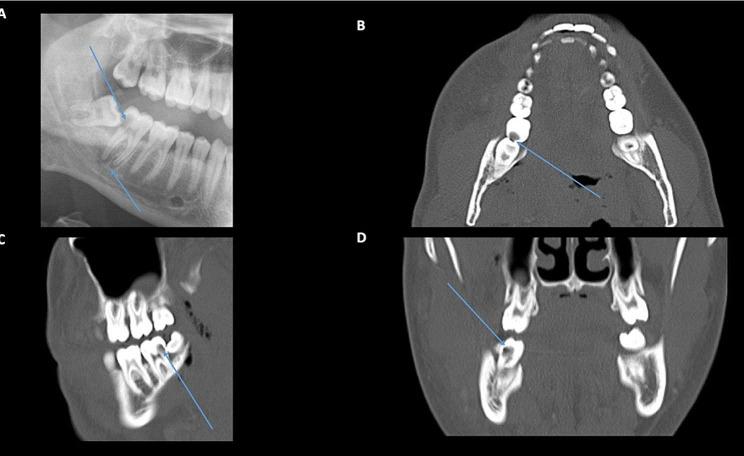

Four patients with odontogenic orbital cellulitis were identified for inclusion. There was an equal proportion of men and women with a mean age of 43 years (range 25-56 years). All patients presented with an orbital compartment syndrome, with visual acuity of counting fingers (n = 1, 25%), hand movements (n = 1, 25%) and no perception of light (n = 2, 50%). The organisms implicated were Streptococcus milleri (n = 3, 75%) and Streptococcus constellatus (n = 1, 25%). MRI findings showed a subperiosteal abscess was present in all cases, which was characterised radiologically as a T1-hyperintense, T2 minimally hyperintense collection with restricted diffusion and a low apparent diffusion coefficient signal. Final visual acuity ranged from 6/6 to no light perception. One patient required an orbital exenteration due to extensive necrosis with sepsis and systemic deterioration.

确定纳入4例牙源性眶蜂窝织炎患者。男女比例相等,平均年龄43岁(范围25 - 56岁)。所有患者均出现眶间隔综合征,视力分别为指数(n = 1,25%)、手动(n = 1,25%)和无光感(n = 2,50%)。涉及的微生物为米勒链球菌(n = 3,75%)和星座链球菌(n = 1,25%)。MRI表现显示所有病例均存在骨膜下脓肿,其影像学特征为T1高信号、T2轻度高信号,弥散受限,表观扩散系数信号低。最终视力范围从6/6到无光感。1例患者因广泛坏死伴脓毒症和全身状况恶化而需要进行眶内容摘除术。